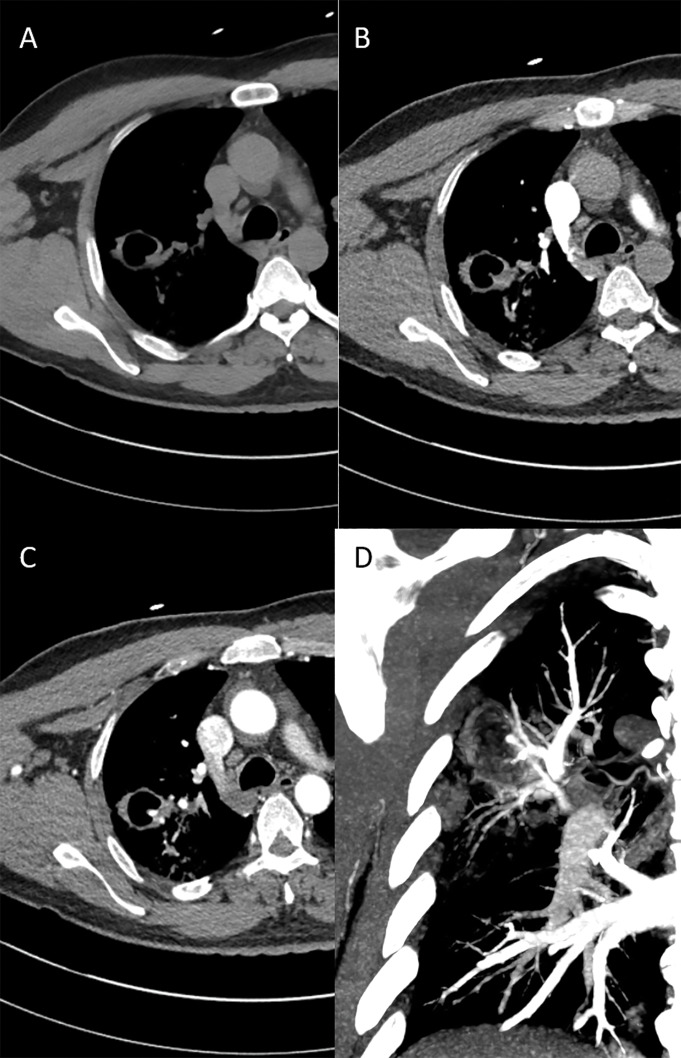

Teaching point: Pulmonary and systemic arterial phases are needed to exclude Rasmussen aneurysm.